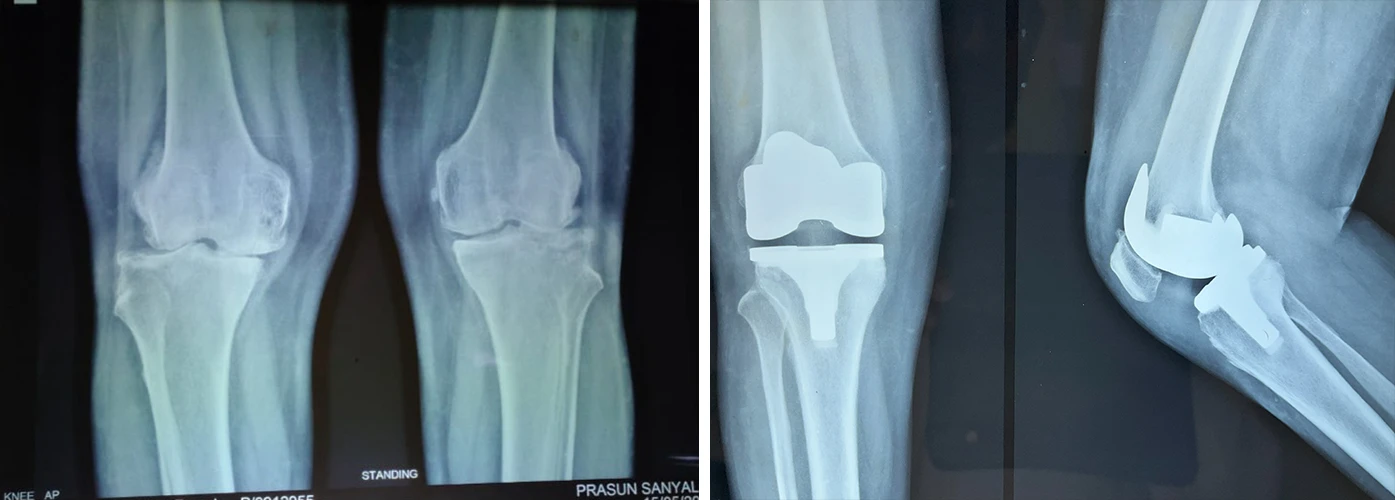

Total Knee Replacement

Are you having pain in your knees? Look no further, because Dr. Sanyal is the best choice for you. He specialises in total knee replacement surgery, offering you a solution to regain your mobility and live pain-free.

Hello

I have done a knee operation on my mother-in-law from Burdwan with Dr. Prasanna Sanyal, now she is very healthy and can walk beautifully. We also liked the doctor’s treatment. Many thanks to Dr. Prasanna Sanyal from our family 😊